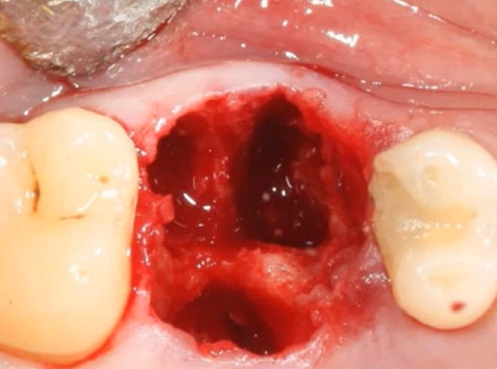

Immediate implantation, especially with immediate loading, often requires placing implants in the socket of an extracted tooth (see photo below). This can lead to bone deficiency and low density, especially in the upper jaw.

An example of a socket from an extracted tooth with an inter-root septum where the implant will be placed. YouTube/ Dr. Sergey Rozhnov /sergiodontolog

And to ensure primary stability in such conditions, there are two options:

- Use cancellous implants with wide-pitch threads that will penetrate deep into the bone

- Compact the bone tissue in the area of the osteotomy using osteotomes and apply a universal implant.